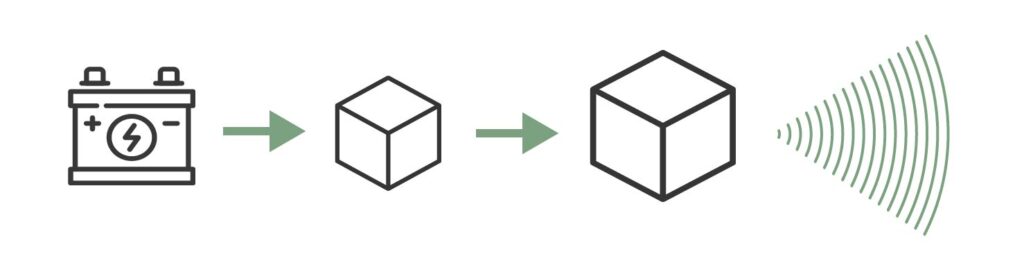

En el caso de los ultrasonidos, necesitaremos una fuente llamada cristal piezoeléctrico. Estos cristales tienen la propiedad de que, al recibir corriente eléctrica, se deforman y comprimen emitiendo ondas de muy alta frecuencia (los ultrasonidos), así como la inversa, generan un campo eléctrico al ser sometidos a deformación mecánica.

Emisión del ultrasonido

El cristal recibe electricidad, se deforma, y esa deformación produce el ultrasonido.

El ultrasonido viaja a través del medio (cuerpo del paciente) y genera ecos a medida que atraviesa el tejido, veremos más adelante cómo interacciona con el mismo.

Recepción del ultrasonido

El cristal recibe el eco del ultrasonido que ha enviado anteriormente, se deforma y genera un impulso eléctrico que puede detectarse.

En función de la intensidad del eco que impacta con el cristal se generan campos eléctricos de diferentes magnitudes que, mediante la informática, se pueden representar en un monitor y producen la imagen de ecografía tal y como la conocemos hoy en día.